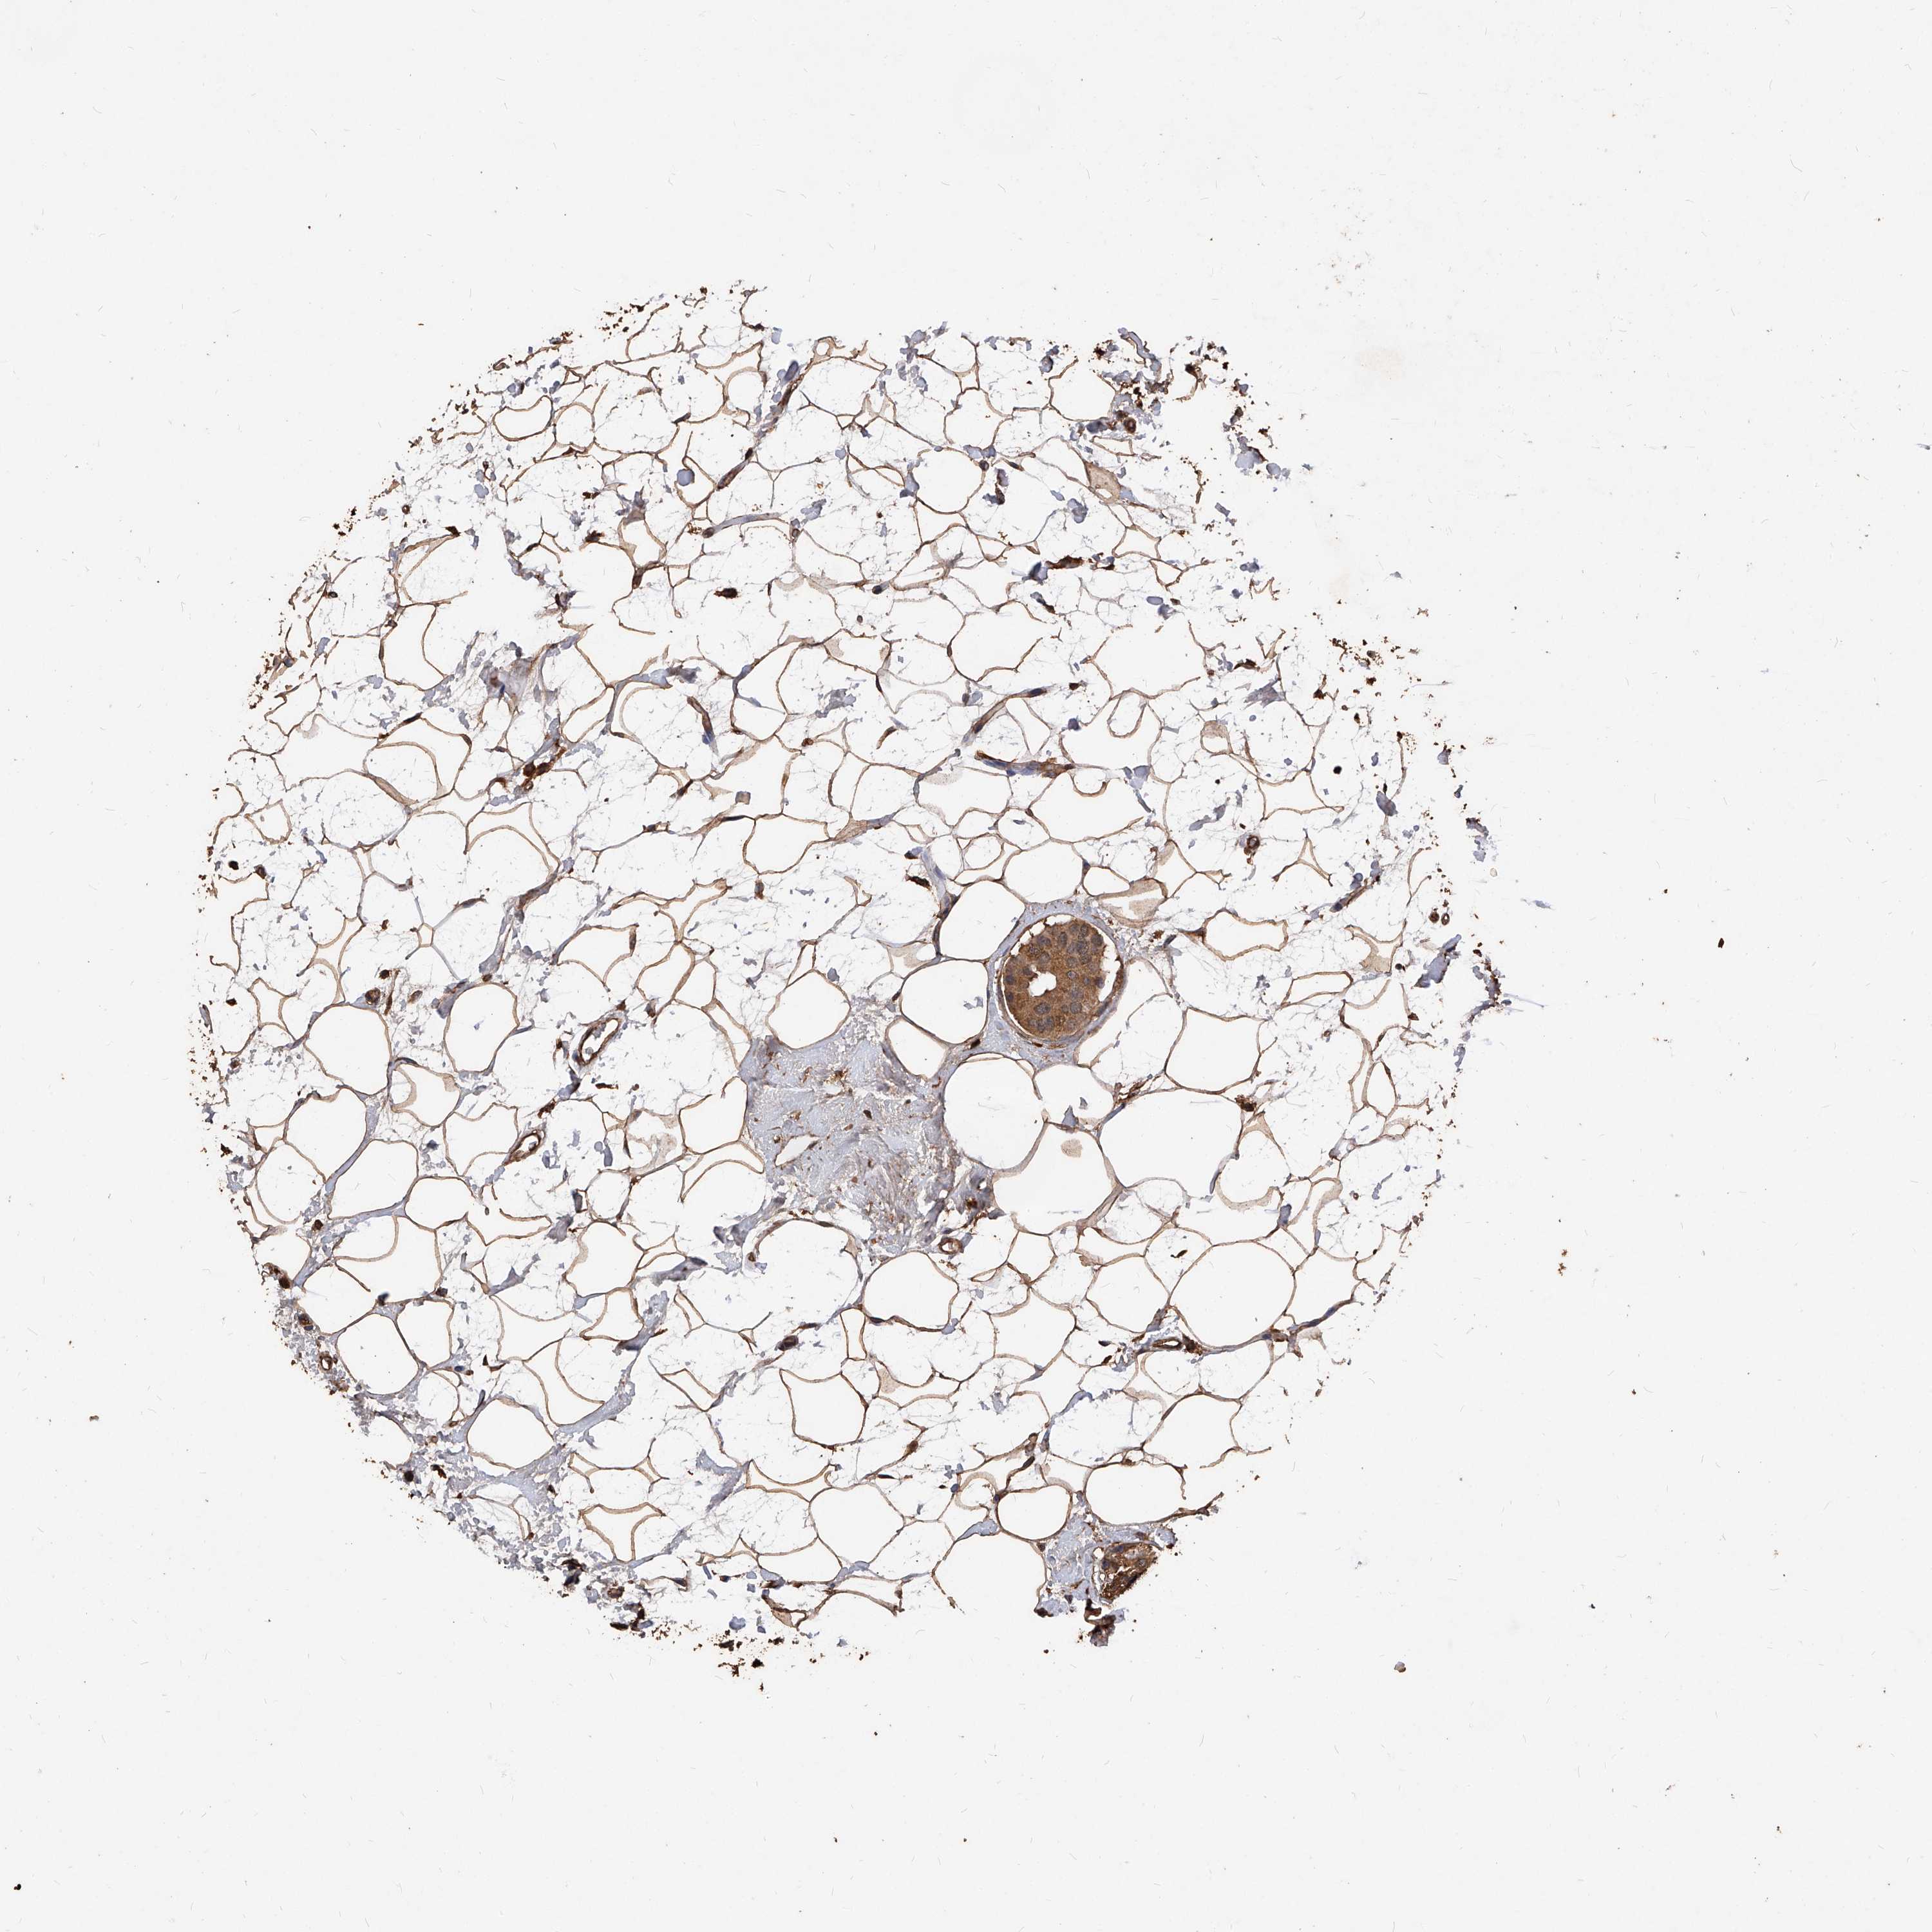

BRCA TCGA BRCA VALIDATION PROTEIN EXPRESSION